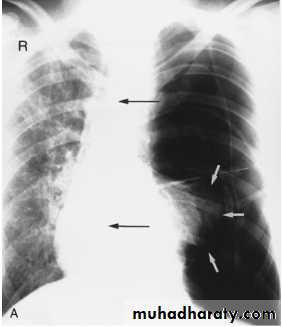

Lingular consolidation-PA. Patchy effacement of the left heart border.

chest practice

Left upper lobe consolidation-Lat.

The opacification is sited anterior to the obliq- fissure-the position of the upper lobe.